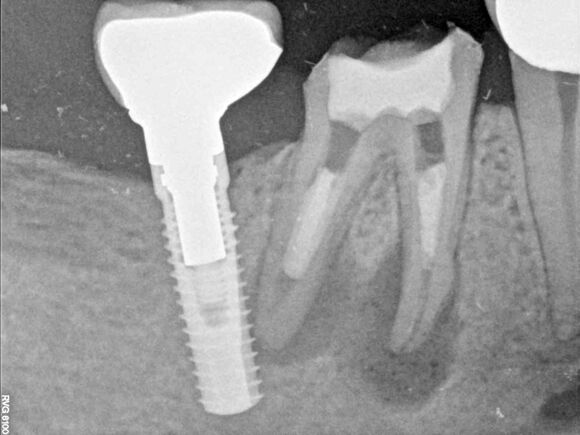

Beispiel 4: Vorher

Unvollständige Wurzelbehandlung und abgebrochenes Instrument.

Beispiel 4: Nachher

Instrument entfernt, Wurzelfüllung optimiert und Entzündung in Rückbildung.